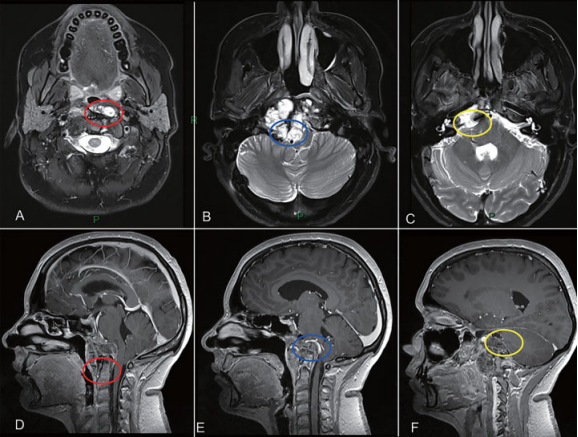

圖1:內(nèi)鏡下鼻內(nèi)鏡入路前的術(shù)前影像。(A-D)MRI T2 WI顯示一個較大脊索瘤延伸至椎前間隙和齒狀突周圍。腫瘤橫向延伸至舌下管和頸靜脈孔,并向內(nèi)側(cè)延伸至硬膜內(nèi)間隙。腫瘤從斜坡中部延伸至樞椎齒狀突周圍。

根據(jù)Carol目前復(fù)雜的病情,福教授及時調(diào)整策略,采取經(jīng)鼻內(nèi)鏡+開顱顯微鏡分階段手術(shù)。一階段經(jīng)鼻內(nèi)鏡切除中線為主的腫瘤,在二個遠外側(cè)入路開顱切除側(cè)方腫瘤,達到較大水平的順利切除腫瘤(▼圖2)。

圖2:顱頸交界區(qū)腫瘤手術(shù)治療策略分析,腫瘤的旁正中部分可以通過經(jīng)鼻內(nèi)鏡手術(shù)切除。樞椎齒狀突周邊腫瘤(A和D處紅色圓圈)、侵犯硬膜內(nèi)部分的腫瘤與后循環(huán)接觸(B和E處藍色圓圈)和先前乙狀竇后入路手術(shù)的粘連(C和F處黃色圓圈),這些部位的腫瘤更適合二期遠外側(cè)開顱手術(shù)。